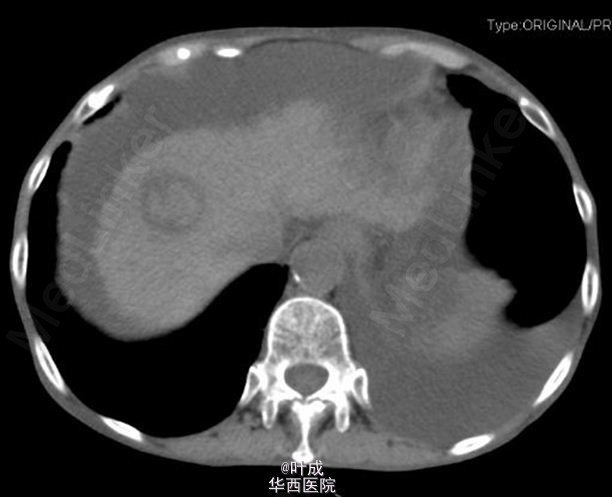

查体:T:37.2℃,P:98次/分,R:18次/分,BP:155/84mmHg,心肺查体无特殊,腹部膨隆,全腹软,上腹部轻压痛,无反跳痛,腹部未触及包块,肝肋下1-2cm,剑下5cm,质地较硬,脾脏肋下未触及,双下肢轻度水肿。 辅助检查:血常规:Hb 96 g/L,WBC 3.86 10^9/L,N 75.3 %;肝肾功:TB 18.0 umol/L,DB 10.7 umol/L,ALT 33 IU/L,AST 109 IU/L,ALB 25.6 g/L,ALP 142 IU/L,GGT 175 IU/L,肾功未见异常;AFP 214.50 ng/ml,CEA 4.23 ng/ml,CA19-9 89.39 U/ml,CA-125 478.40 U/ml;输血前检查:乙肝表面抗体、乙肝e抗体、乙肝核心抗体阳性,余阴性,高精度HBV病毒载量 阳性,<20 IU/mL;凝血常规、大小便常规未见异常;腹水常规示黄色微混,有核细胞 20 10^6/L,总蛋白 12.6 g/L。腹部增强CT:肝硬化,腹水,食管-胃底粘膜下、胃周静脉曲张,脾大;右半结肠肿胀,肝门区、肠系膜根部及腹主动脉周围淋巴结增多,部分增大,自发性腹膜炎?与旧片比较腹水明显增多,淋巴结明显增多。肝右前叶上段片团影,肝右前叶上段见一大小约2.8×2.8cm的稍低密度影,其内见稍高密度影,边界模糊,增强扫描呈不均匀强化(图1-3)。